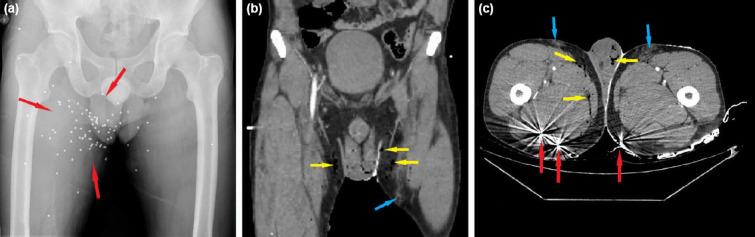

In the study, 1225 patients were evaluated, and 98.7% of them were women (mean age 35 [IQR: 17] years). Of the pa-tients, 63.1% were high school and university graduates. The rate of married women was 74.6%. No relationship was found between gender, age, educational status, and marital status (p>0.05). Most of the traumas were minor (85.4%) and blunt (81.9%) trauma, and the most common types of trauma were kicking (49.9%) and punching (47.3%). It was found that the most frequently affected areas of the patients were the head and neck (76.7%), and the frequency of pelvic trauma was high in male patients (p<0.05). The most com-mon bone fracture was nasal (40.5%) followed by ulna fractures (14.5%). The left-sided diaphyseal fractures were the most common in patients exposed to IPV. In our study, the frequency of mortality was 12.9%, and it was found to be significantly higher in males (p<0.05).

本研究共评估了 1225 名患者,其中 98.7%为女性(平均年龄 35 [IQR:17] 岁)。患者中 63.1%为高中和大学毕业生。已婚女性的比例为 74.6%。性别、年龄、教育程度和婚姻状况之间无相关性(p>0.05)。大多数创伤为轻微(85.4%)和钝性(81.9%)创伤,最常见的创伤类型为踢打(49.9%)和拳打(47.3%)。发现患者最常受影响的部位是头部和颈部(76.7%),男性骨盆创伤发生率较高(p<0.05)。最常见的骨折是鼻骨(40.5%),其次是尺骨骨折(14.5%)。在 IPV 暴露的患者中,左侧骨干骨折最为常见。在本研究中,死亡率为 12.9%,男性死亡率明显较高(p<0.05)。